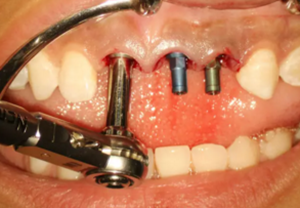

圖9 植入種植體

(2)即刻種植、即刻臨時修復(fù)。術(shù)中不翻瓣微創(chuàng)拔除牙根,牙槽 窩骨壁完整。在多級導(dǎo)板輔助下完成種植窩洞制備,植入Bego柱形種植 體,型號分別為:上頜右側(cè)中切牙位點(diǎn)4.1mm×15mm、上頜左側(cè)中切牙 位點(diǎn)?3.75mm×15mm、上頜左側(cè)側(cè)切牙位點(diǎn)3.25mm×15mm,扭矩均為 35N·cm。種植體與唇側(cè)骨壁間隙約2mm,植入Bio-Oss®Collagen骨膠 原。戴入橋用鈦臨時基臺,臨時冠就位順利,自凝樹脂口內(nèi)粘接后適當(dāng)修整 外形,充分磨光,調(diào) 至正中 、前伸 和側(cè)方 與對頜牙均無接觸。術(shù)后 根尖片顯示種植體位置、方向良好。